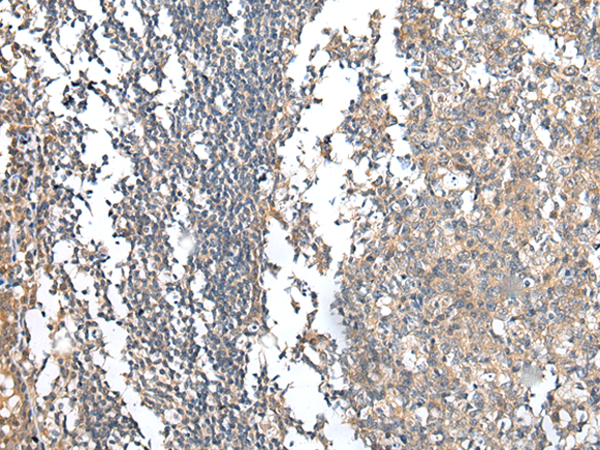

分类: 科研抗体货号: P02184别名: TSC; CHP3应用: IHC反应种属: Human, Mouse